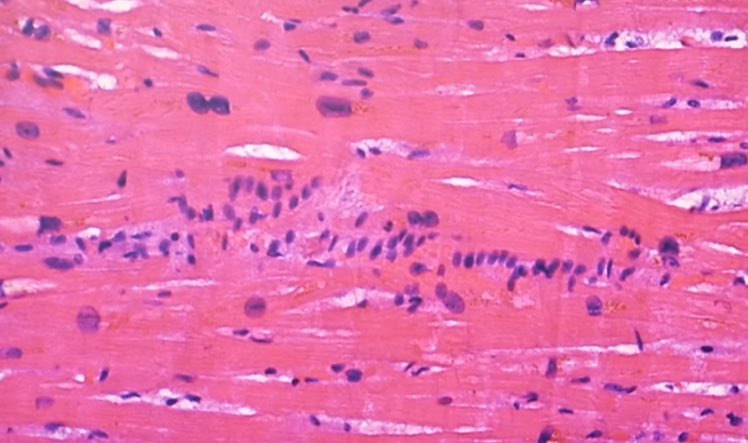

التهاب عضلة القلب اللمفاوي ، التهاب غشاء القلب ، التهاب التامور ، "غلبة الخلايا الليمفاوية" :

⁃نموذجي للعدوى الفيروسية

⁃يصعب التعرف عليها بالميكروسكوب ،

⁃غالبًا ما يُساء تفسيرها من الناحية النسيجية على أنها معدية (الخلايا الحبيبية!). 6️⃣

⁃عادةً ما تكون البؤر صغيرة متعددة ، وبالتالي لا يتم اكتشافها في كثير من الأحيان

⁃التأثير على قدرة الضخ (تحذير: وزن القلب الحرج)

⁃فشل القلب في الجهاز عندما يتأثر نظام التوصيل ؛ "الموت القلبي المفاجئ" ، الاكتشاف بالكاد ممكن (حوالي 15000 قسم)7️⃣